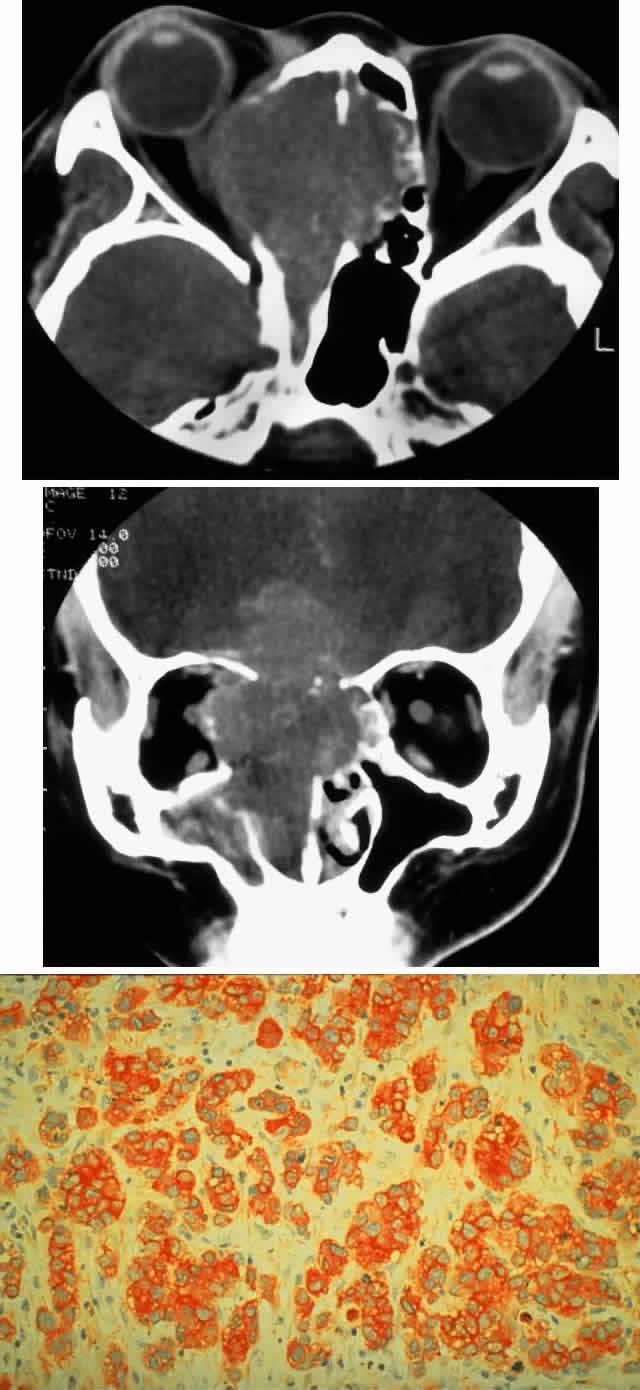

Extrascleral extension occurs in 10% to 15% of patients with uveal melanomas118–120 and may present clinically as a visible anterior nodule, as proptosis in patients with known intraocular tumor (Fig. 13), with phthisis and unsuspected tumor, or as a mass in orbital recurrence. Orbital recurrence associated with hepatic metastasis has been described as late as 42 years after primary enucleation.121 Orbital extension may only become evident at the time of surgery; however, the use of ultrasonography and CT scan may lead to increasing preoperative detection of extrascleral nodules.

Fig. 13. A 65-year-old man presented originally with a right retinal detachment and secondary glaucoma due to a large choroidal melanoma. The patient refused enucleation and self-treated instead with herbal medicines and “health foods.” He presented again 6 years later with acute onset of proptosis associated with pain, periocular edema, erythema, and marked restricted ductions (A). CT scan revealed the intraocular tumor, with massive orbital extension and displacement of the globe anteriorly, downward, and laterally (B and C). He underwent lid-splitting exenteration and split-thickness skin graft from the anterior thigh. The gross specimen shows the massive orbital component of melanoma, which had extended from the posterior choroid through emissarial vessels (D). An area of predominantly spindle-shaped melanoma cells with scattered, heavily pigmented macrophages is shown (E) (H & E, × 200). (D and E courtesy of Valerie A. White, MD, Department of Pathology, University of British Columbia, and the Vancouver Hospital and Health Sciences Center.)